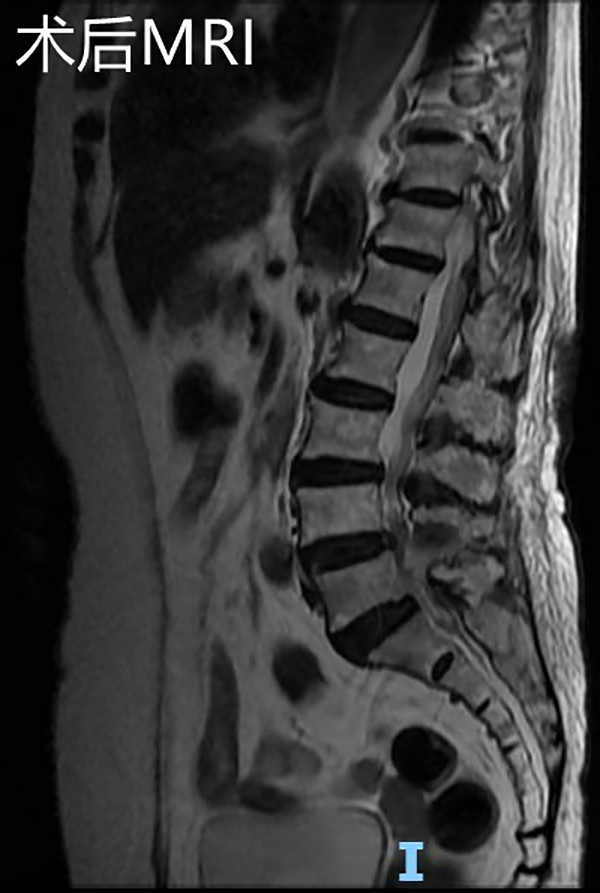

手術(shù)后復(fù)查腰椎MRI顯示:相應(yīng)的椎管狹窄及神經(jīng)根壓迫已解除,手術(shù)后第2天邱奶奶便可下地行走,腰痛及左下肢疼痛緩解,復(fù)查腰椎磁共振見(jiàn)L4/5左側(cè)狹窄已完全解除。手術(shù)后第4天,患者順利出院,沒(méi)有出現(xiàn)任何手術(shù)并發(fā)癥。